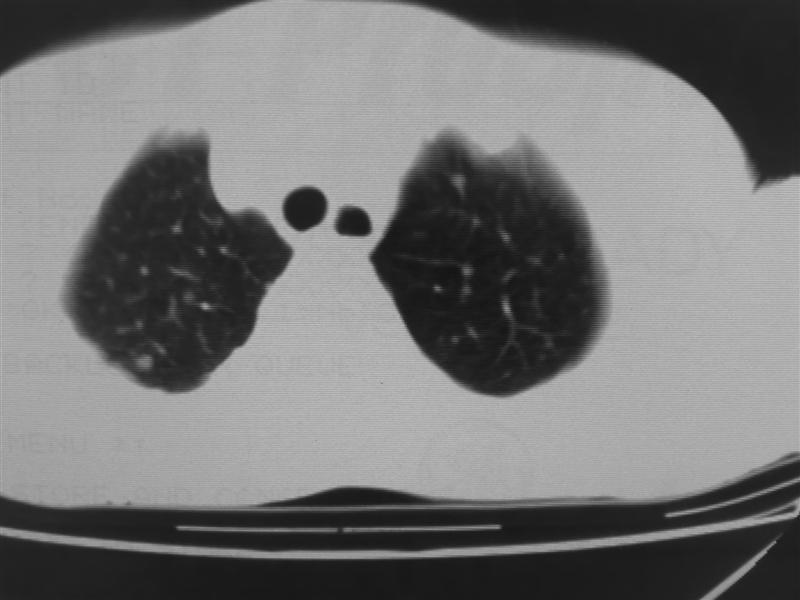

标题: CT10080:F76Y,各位老师发表高见!!! [打印本页]

标题: CT10080:F76Y,各位老师发表高见!!!

怎么没有病史呢?支持:考虑肺癌,肺、胸膜转移可能性大.

考虑肺癌,肺、胸膜转移可能性大。病史一定要尽量完整。

有病史吗,应该是肺癌半转移吧